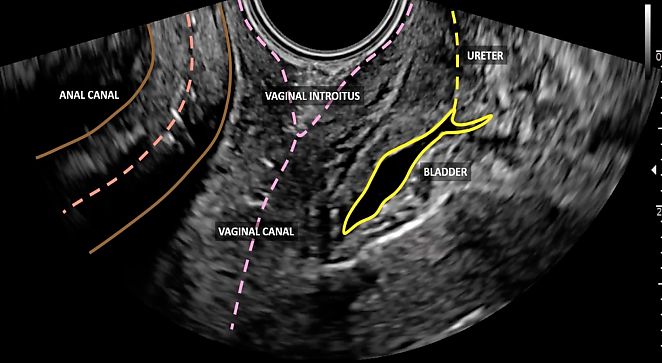

During this initial phase, the anorectal canal, the rectovaginal septum, the urethra and the vesicovaginal septum are also visualized (Figure 1). The vesicovaginal septum can be evaluated in a midsagittal section by pressing the uterus and vagina against the bladder (Video 1). Similarly, the rectovaginal septum can be assessed in a midsagittal section by pressing the probe against the rectum and vagina (Video 2). These movements allow the assessment of tissue elasticity and mobility in relation to surrounding tissues and organs, which is important to evaluate in the context of both benign (e.g. endometriosis) and malignant (e.g. neoplastic infiltration from cervical cancer) gynecological conditions.6

1

Visualization of pelvic structures from the vaginal introitus.